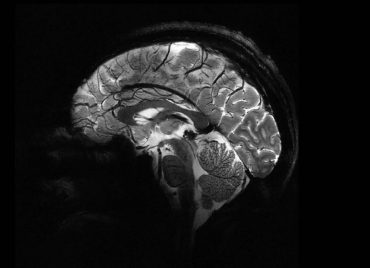

4분 만에 고해상도 뇌 촬영 가능한 MRI

이석원 기자

2024년 4월 12일